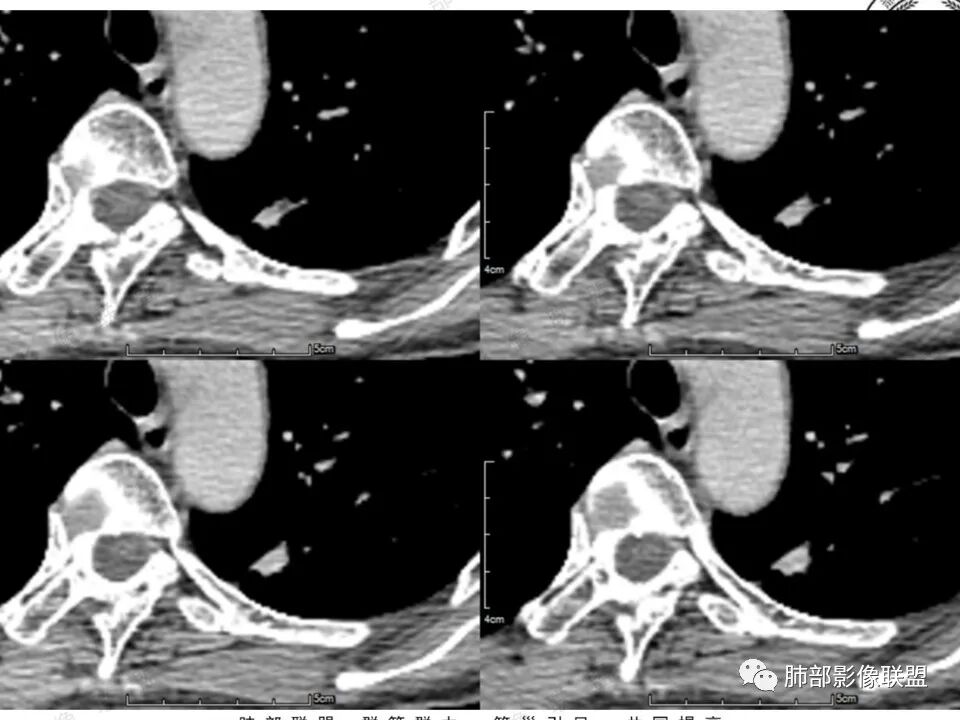

高强化,实性结节,边缘有磨玻璃,有膨隆,斜裂侧偏平直胸膜凹陷,IAC,鉴别炎性肉芽肿

左肺上叶长条状病灶,胸膜牵拉,边缘平直,磨玻璃边界清楚,不均匀强化,考虑炎性,不完全排除肺癌

左肺结节,形态不规则,边缘略收缩,分叶,部分边缘平直,周围可见清晰磨玻璃影,增强后明显强化,考虑:血管瘤,炎性假瘤,鉴别腺癌

左肺上叶尖后段病灶,毛玻璃边界不清,实性成分边缘平直,重建,病灶长条形,增强明显强化,考虑炎症

中年女,左肺结节,边缘平直,明显持续不均匀强化,周围略毛糙,考虑IMT

中年女性,左肺上叶长条状病灶,宽基底与胸膜交界,胸膜凹陷,病灶边缘平直,局部收缩及膨隆,周围可见磨玻璃,其边界清楚,增强病灶不均匀强化,影像表现有炎性病变,也有明显占位表现,考虑OP,有膨胀性表现的小结节,不完全排除肺癌!需要结合相关检查。

晨读:中年女性,体检发现,左肺上叶结节,形态不规则,呈长条状,分叶,部分边缘平直,周围可见磨玻璃影,增强后明显强化,首先考虑良性病变:1、炎性病变。2、血管瘤。

中年女性,查体发现左上肺条块结节,靠近斜裂,边缘平直有收缩,胸膜牵拉,明显强化,考虑炎性假瘤或炎性肉芽肿,鉴别腺癌。

中年女性,体检发现。左肺上叶后段不规则结节灶,密度不均匀,病灶周围可以边界似清非清毛玻璃影,临近胸膜牵拉,增强扫描病灶明显不均匀强化。考虑炎性假瘤,鉴别腺癌。

患者中年女性,体检发现。胸部CT:左肺上叶后段长条形结节灶,边缘光滑,边界清楚,见分叶、毛刺、胸膜牵拉及平直征象。增强明显强化,内可见血管增粗,综合考虑恶性病变,浸润性腺癌可能大,鉴别结核。